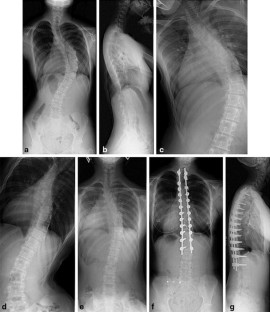

Surgical treatment of double thoracic adolescent idiopathic scoliosis with a rigid proximal thoracic curve

There is limited consensus on the optimal surgical strategy for double thoracic adolescent idiopathic scoliosis (AIS). Recent studies have reported that pedicle screw constructs to maximize scoliosis correction cause further thoracic spine lordosis. The objective of this study was to apply a new surgical technique for double thoracic AIS with rigid proximal thoracic (PT) curves and assess its clinical outcomes.

Twenty one consecutive patients with Lenke 2 AIS and a rigid PT curve (Cobb angle ≥30º on side-bending radiographs, flexibility ≤30 %) treated with the simultaneous double-rod rotation technique (SDRRT) were included. In this technique, a temporary rod is placed at the concave side of the PT curve. Then, distraction force is applied to correct the PT curve, which reforms a sigmoid double thoracic curve into an approximate single thoracic curve. As a result, the PT curve is typically converted from an apex left to an apex right curve before applying the correction rod for PT and main thoracic curve.

All patients were followed for at least 2 years (average 2.7 years). The average main thoracic and PT Cobb angle correction rate at the final follow-up was 74.7 and 58.0 %, respectively. The average preoperative T5–T12 thoracic kyphosis was 9.3°, which improved significantly to 19.0° (p < 0.0001) at the final follow-up. Although 71 % patients had preoperative level shoulders or a positive radiographic shoulder height, all patients had mildly imbalanced or balanced shoulders at the final follow-up. The average preoperative main thoracic apical vertebral rotation angle of 20.7° improved significantly after surgery to 16.4° (p = 0.0046), while the average preoperative total SRS questionnaire score of 3.7 improved significantly to 4.4 (p = 0.0012) at the final follow-up.

Radiographic findings and patient outcomes were satisfactory. Thoracic kyphosis can be maintained or improved, while coronal and axial deformities can be corrected using SDRRT for Lenke 2 AIS with a rigid PT curve.